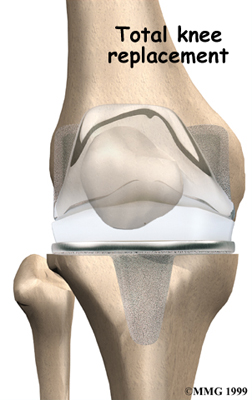

Artificial Knee Replacement

An artificial knee replacement is the ultimate solution for advanced knee OA.

Surgeons prefer not to put a new knee joint in patients younger than 60. This is because younger patients are generally more active and might put too much stress on the joint, causing it to loosen or even crack. A revision surgery to replace a damaged prosthesis is harder to do, has more possible complications, and is usually less successful than a first-time joint replacement surgery.

Related Document: FYZICAL Glenpool's Guide to Artificial Joint Replacement of the Knee